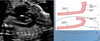

Images 6 and 7

LONGITUDINAL and SAGITTAL VIEWS

IMAGE A: DUCTAL ARCH

IMAGE B: AORTIC ARCH

how is LONGITUDINAL / SAGITTAL VIEWS OF THE

THIS VIEW IS OBTAINED BY CONTINUING TO ROTATE THE TRANSDUCER FROM THE

LONG-AXIS VIEW OF THE LEFT VENTRICLE TO AN ALMOST SAGITTAL VIEW OF THE

FETUS.

THIS RESULTS IN THE “HOCKEY STICK” APPEARANCE OF THE PULMONARY ARTERY

- DUCTUS OUTFLOW TRACT.